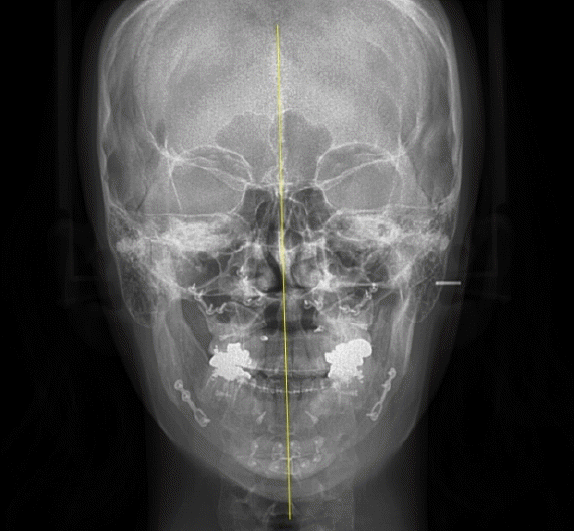

28세 여성이 안면비대칭과 턱관절의 불편감으로 내원하였다. 안모는 우측으로 비대칭이 관찰되었으며, 우측 턱관절부위의 관절잡음이 있었으며 26mm 개구 시 과두걸림이 있었다. 최대개구량은 48mm이고 우측으로 변위된 개구 양상을 보였다. 안면 CT와 X-ray 촬영 결과, 좌측 하악지가 우측 하악지에 비해 12.89mm 길었으며 관절까지의 방향이 우측 하악지에 비해 외측으로 향해 있는 것을 알 수 있었다(Fig. 1). 우측 하악체의 길이가 좌측에 비해 길고 이로 인해 하악 턱끝은 정중선에 비해 우측으로 13.8mm 편위되어 있었다. 그리고 교합평면은 좌측으로 기울어지고 구치부 반대교합과 전치부 절단교합이 존재하였다(Fig. 2). 안면비대칭과 턱관절원판의 정복성 전방변위로 진단하고 하악골의 비대칭과 교합평면의 개선을 위해 턱교정수술과 치아교정술을 계획하였다. 턱교정수술은 상악골 후상방(좌측: 3.5mm, 우측: 4.5mm)이동하고, 하악골은 후방(좌측: 17.5mm, 우측: 5.5mm) 이동하였다(Fig. 3). 턱끝성형술과 하악골 윤곽성형술을 통해 하악골과 안모의 대칭에 도움을 주었다. 하악골수술은 시 시상분할절골술을 이용하였으며, 관절과두가 포함된 근심골편을 재위치시켜주어 과두걸림을 해소하려 하였다. 수술 2주후 치아교정술을 시작하면서 개구연습을 진행하였으며 비대칭적 개구 습관의 교정을 위해 탄성고무줄을 이용하여 중심선에 맞게 진행하였다. 수술 6개월 후 평가 시, 안모의 비대칭은 개선된 결과를 보였으며(Fig. 4) 턱관절 부위의 과두걸림은 관찰되지 않고 정상범위 내의 개구 양상을 보였다.- 증례 2

Figure 1.

A. 3D facial CT (frontal view). B. 3D facial CT (submentovertex view). C. Panoramic radiograph.